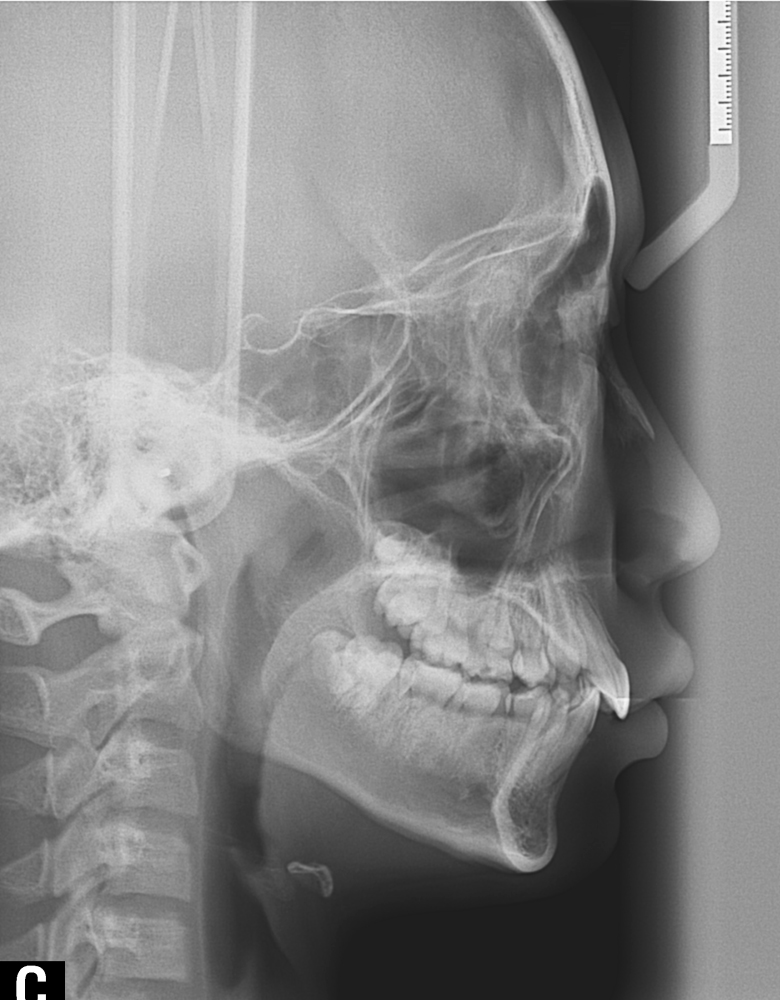

À§ ȯÀÚ´Â À´Ï°¡ ¾Æ·§´Ï¸¦ ³Ê¹« µ¤¾î¿ä(°ú°³±³ÇÕ) ¸¦ ÁÖ¼Ò·Î ³»¿øÇÑ ÃʵîÇлýÀ̾ú½À´Ï´Ù. ÅμºÀå ¾ÇÁ¤ÇüÀåÄ¡ »ç¿ëÈÄ È£ÈíÀÌ °³¼± µÇ¾úÀ¸¸ç Ä¡·áÀü¿¡ ºñÇØ ۰¡ 10cmÁ¤µµ ±Þ¼Ó ¼ºÀåÇÏ¿´½À´Ï´Ù.

°ú°³±³ÇÕ°ú ¹«ÅÎ,ÅΰüÀýÀ» ÁÖ¼Ò·Î ³»¿øÇÏ¿© ÅμºÀå ¾ÇÁ¤ÇüÀåÄ¡¸¦ ÀÌ¿ëÇÏ¿© Ä¡·áÁßÀΠȯÀÚ·Î Ä¡·á½ÃÀÛ½ÃÁ¡ ±âÁØÀ¸·Î ÇöÀç ۰¡ ¾à 8cmÁ¤µµ ¼ºÀåÇÏ¿´½À´Ï´Ù. (Âü°í·Î 2³âÂ÷ ¿©µ¿»ý°ú ۰¡ 7-9cmŰ Â÷À̳²)